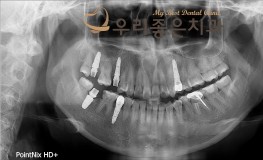

우리좋은치과 치아 상실 및 골소실 → 뼈이식 및 임플란트 보철 치료 (김** 201..

No.345

임플란트

2019-11-25

1552